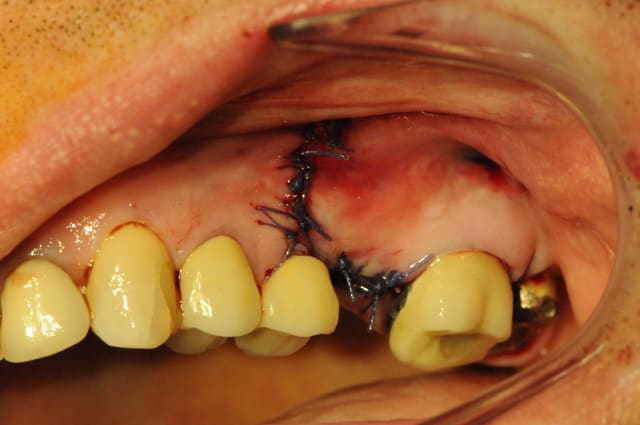

Beau travail dentiste 57. Je ne compte pas commenter l'indication du sinus-lift mais plutot la chirurgie en elle même.

J'ai cependant quelques remarques et certainement quelques conseils pour tes prochains sinus-lift :

- position de la fenêtre latérale : il est pratique de mesurer sur l'OPG ou le scanner la hauteur de crête et de reporter cette mesure in situ, cela t'éviteras de taper dans la corticale et d'avoir un accès décalé et plus génant. Dans le cas où la hauteur de crête est très fine 2-3 mm, il est dans tous les cas fortement conseillé de rester à un minimum de 5mm de cette dite crête et ce afin d'éviter un effondrement crestal difficile à régénerer.

- taille de la fenêtre latérale : elle est dans ton cas acceptable même si j'ai l'habitude d'ouvrir un peu plus ... accès et élévation en sont facilités.

- volet osseux : de par ta préparation à la fraise boule il t'était impossible de repositionner le volet osseux en fin de chirugie. La logique voudrait que tu repousses ce volet dans le sinus afin de créer un "pseudo plafond sinusien". A la vue de tes photos il semblerait que tu es tout de même enlevé ce volet. Est ce que je me trompe ? si oui oublies ma question, si non pourquoi ?

- fracture d'insert mectron : quel est la référence de l'insert qui s'est cassé. Sous quel programme s'est il cassé? J'utilise le mectron pratiquement tous les jours. J'ai en 4 ans d'utilisation cassé un seul insert et par ma faute puisque j'ai alors utilisé un programme inadapté à l'insert.

- implantation simultanée : comme amibien le décrit j'aurais également dans ton cas opté pour une mise en place implantaire dans la foulée puisqu'il n'y a aucun doute à la vue de ton OPG qu'une stabilité primaire aurait été obtenue sans problème avec un implant conique.

- membrane de recouvrement : comme je l'ai écrit dans une autre post, plusieurs review de qualité s'accordent à dire que la recouvrement de la fenêtre d'accés est en corrélation avec un taux de survie implantaire amélioré à long terme. Je n'ai donc rien à te reprocher à ce niveua là. Cependant, j'aurais dans ton cas deplacé mon incision de décharge en mésial de la 25 afin d'éviter d'avoir ma limite membranaire en dessous de mon trait d'incision. Cela évite des complications d'éventuelle exposition si un point lache.